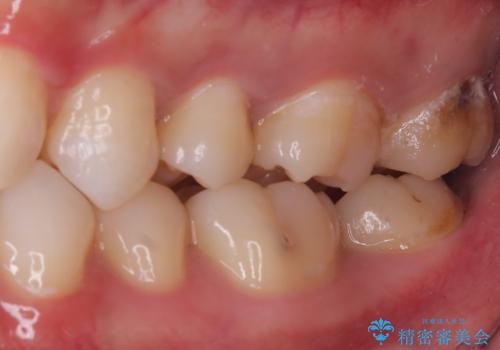

左上一番奥の歯の頬側に実質欠損を伴う虫歯が存在したため、セラミックインレーでの治療となりました。

上顎左側第二大臼歯頬側面から遠心面、咬合面にもう蝕が波及していたためアンレー形態となりました。

清掃しずらい箇所ではあるため、汚れが付きづらい適合性のよいセラミック素材を選択しました。